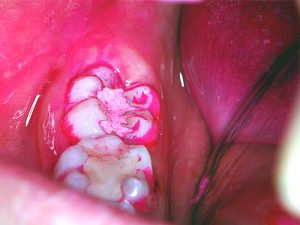

蔗糖20%の培地を作り、HY剤配合セメントで仮封した永久歯を入れ37℃で培養しました。2日後のコントロール群では、多量の歯垢が付着しています。

(図3)しかし、実験群の歯の表面には歯垢が付着していますが、セメントの上には見られません。(図4)4日後では、セメントの上にも付着が始まりました。このことからHY剤配合セメントには、歯垢の付着を抑制する効果があることがわかりました。(図5)タンニンの“抗菌作用”・“抗酸化作用”は、ヒトの口の健康にも影響をおよぼしていたのです。

図4